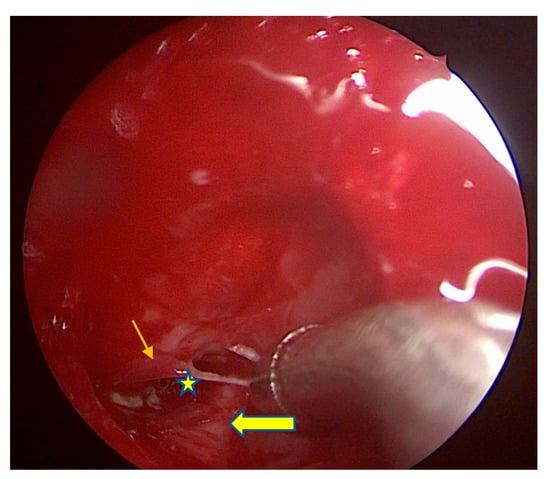

Figure 2.

The view into the right sphenoid sinus. Thin arrow represents the foramen rotundum. Thick arrow represents the vidian canal. Star represents the tight opening into the lateral recess. The curved suction tip is too large to pass through the narrow opening into the lateral recess.